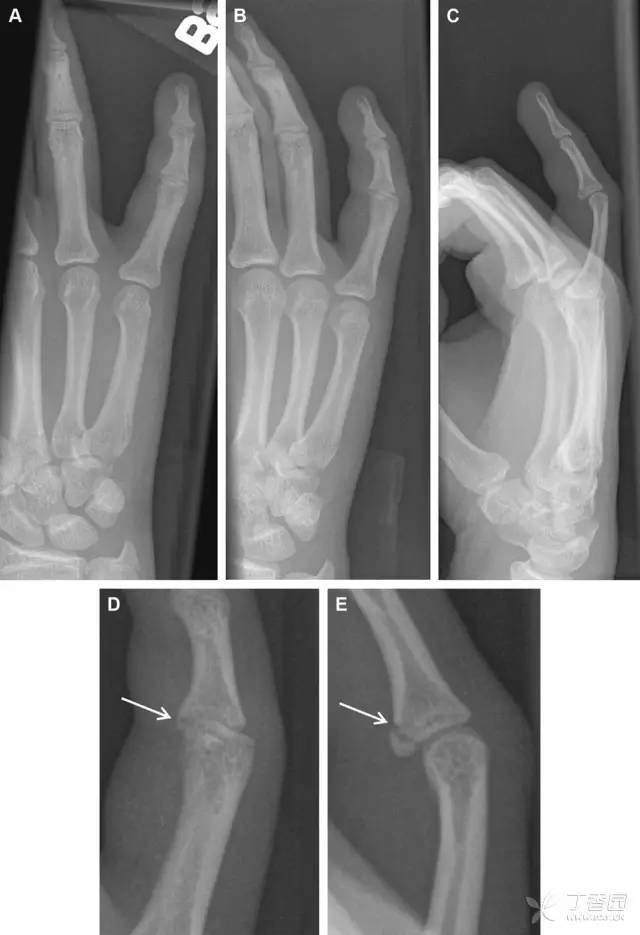

32 掌板骨折

掌板是掌指关节和指间关节关节囊掌侧的纤维结构,防止关节过伸。掌板的远端部是增厚的纤维软骨,附着于指骨掌侧基底部,而其两侧与侧副韧带的纤维融合。掌板骨折多发生于过伸损伤,为撕脱性骨折。

图 3 掌板骨折(A~C)小指前后位、斜位、侧位片,由于骨折的部位及特点,在前后位片上通常难以发现骨折;放大后的斜位(D)、侧位(E)可见一骨碎片(白色箭头)